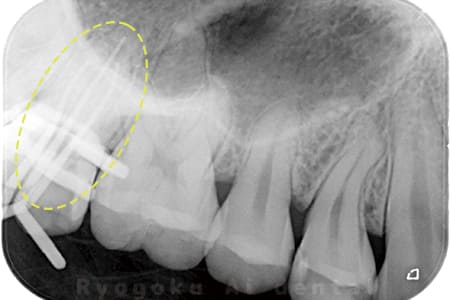

根管内の異物

- 原因

- 根管内異物(ファイル破折)による慢性根尖性歯周炎

- 治療期間

- 3ヶ月

- 治療内容

- マイクロスコープを使用した根管内異物除去並びにマイクロエンド

- 治療費用

- 121,000円(ファイル除去費用も込み)

他院で細い器具(ファイル)が根管内に破折した状態で、咬合痛を主訴に来院された患者様です。ファイルをマイクロスコープ下で除去し、根管治療を行ないました。